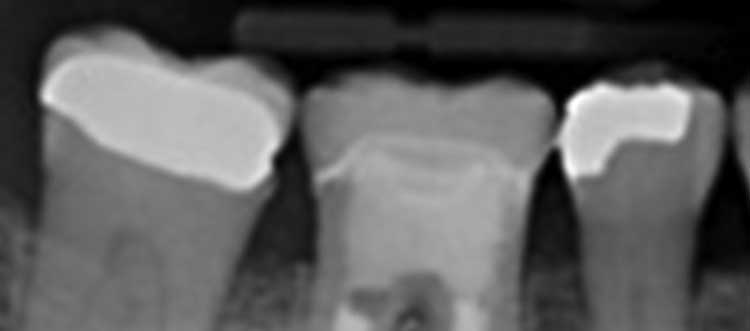

Return to "Using Endodontic Therapy And an Endocrown to Treat Patients on Bisphosphonates" 1121-did-endodontic-therapy-6 Next Previous